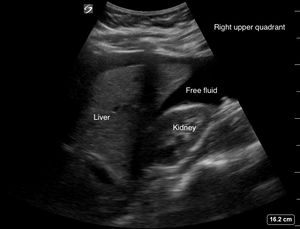

A 19-year-old female, gravida 1 para 0 at 7-weeks 3-days gestation by last menstrual period, consistent with recent (6-week 2-days) ultrasound, presented to the emergency department (ED) for evaluation after a syncopal episode with associated abdominal pain. She also noted intermittent vaginal bleeding over the previous week. She reports a normal intrauterine pregnancy (IUP), as determined by ultrasound, during a recent obstetrical workup for her pregnancy. Her vital signs on arrival were as follows: blood pressure 98/46 and heart rate 69 bpm, with a normal temperature, respiratory rate, and oxygen saturation. She was noted to be guarding on abdominal exam and had both tenderness to palpation and rebound tenderness. Her past medical history was significant for a diagnosis of chlamydia and bacterial vaginosis. A Focused Assessment with Sonography in Trauma (FAST) exam via point-of-care ultrasound (POCUS) was performed in the ED (Figures 1, 2 and 3).1

An intrauterine pregnancy with fetal cardiac activity was noted on ED POCUS. An extrauterine pregnancy could not be excluded. Due to a positive FAST scan (fluid in the RUQ), the findings and clinical presentation were concerning for a possible heterotopic pregnancy consisting of a viable IUP and a ruptured ectopic pregnancy. The Ob-Gyn team was consulted while she was being resuscitated with blood products in the ED, and she was promptly taken to the operating room for an exploratory laparotomy. This revealed approximately 2 liters of hemoperitoneum. She underwent a left salpingectomy for a ruptured ectopic pregnancy. She did well during her post-operative course and was discharged home on post-op day 3. She subsequently had a spontaneous vaginal delivery of a viable infant at 37 weeks.